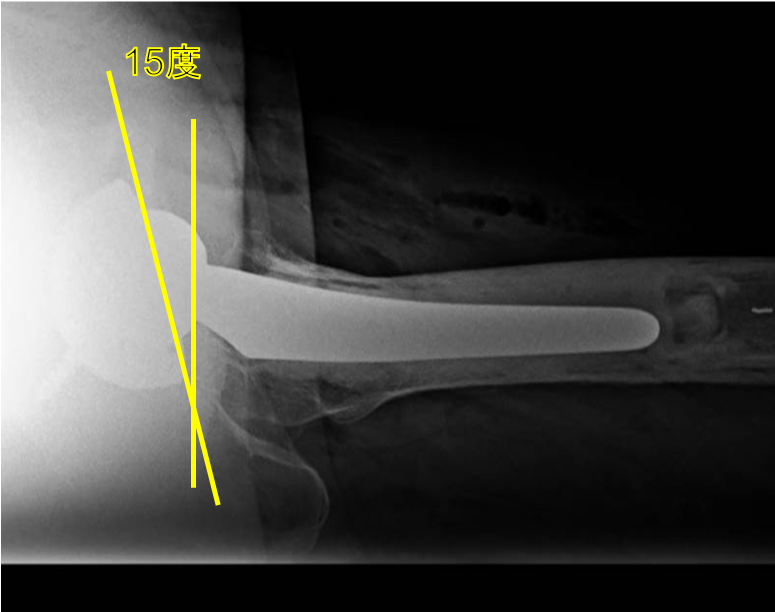

そのためにはインプラントの正確な設置も非常に重要となります。 股関節のカップの設置の理想は、正面から見て、外側に40度、側面から見て、前側に15度の角度がついているものが脱臼リスクの最も少ない理想の設置と言われています。